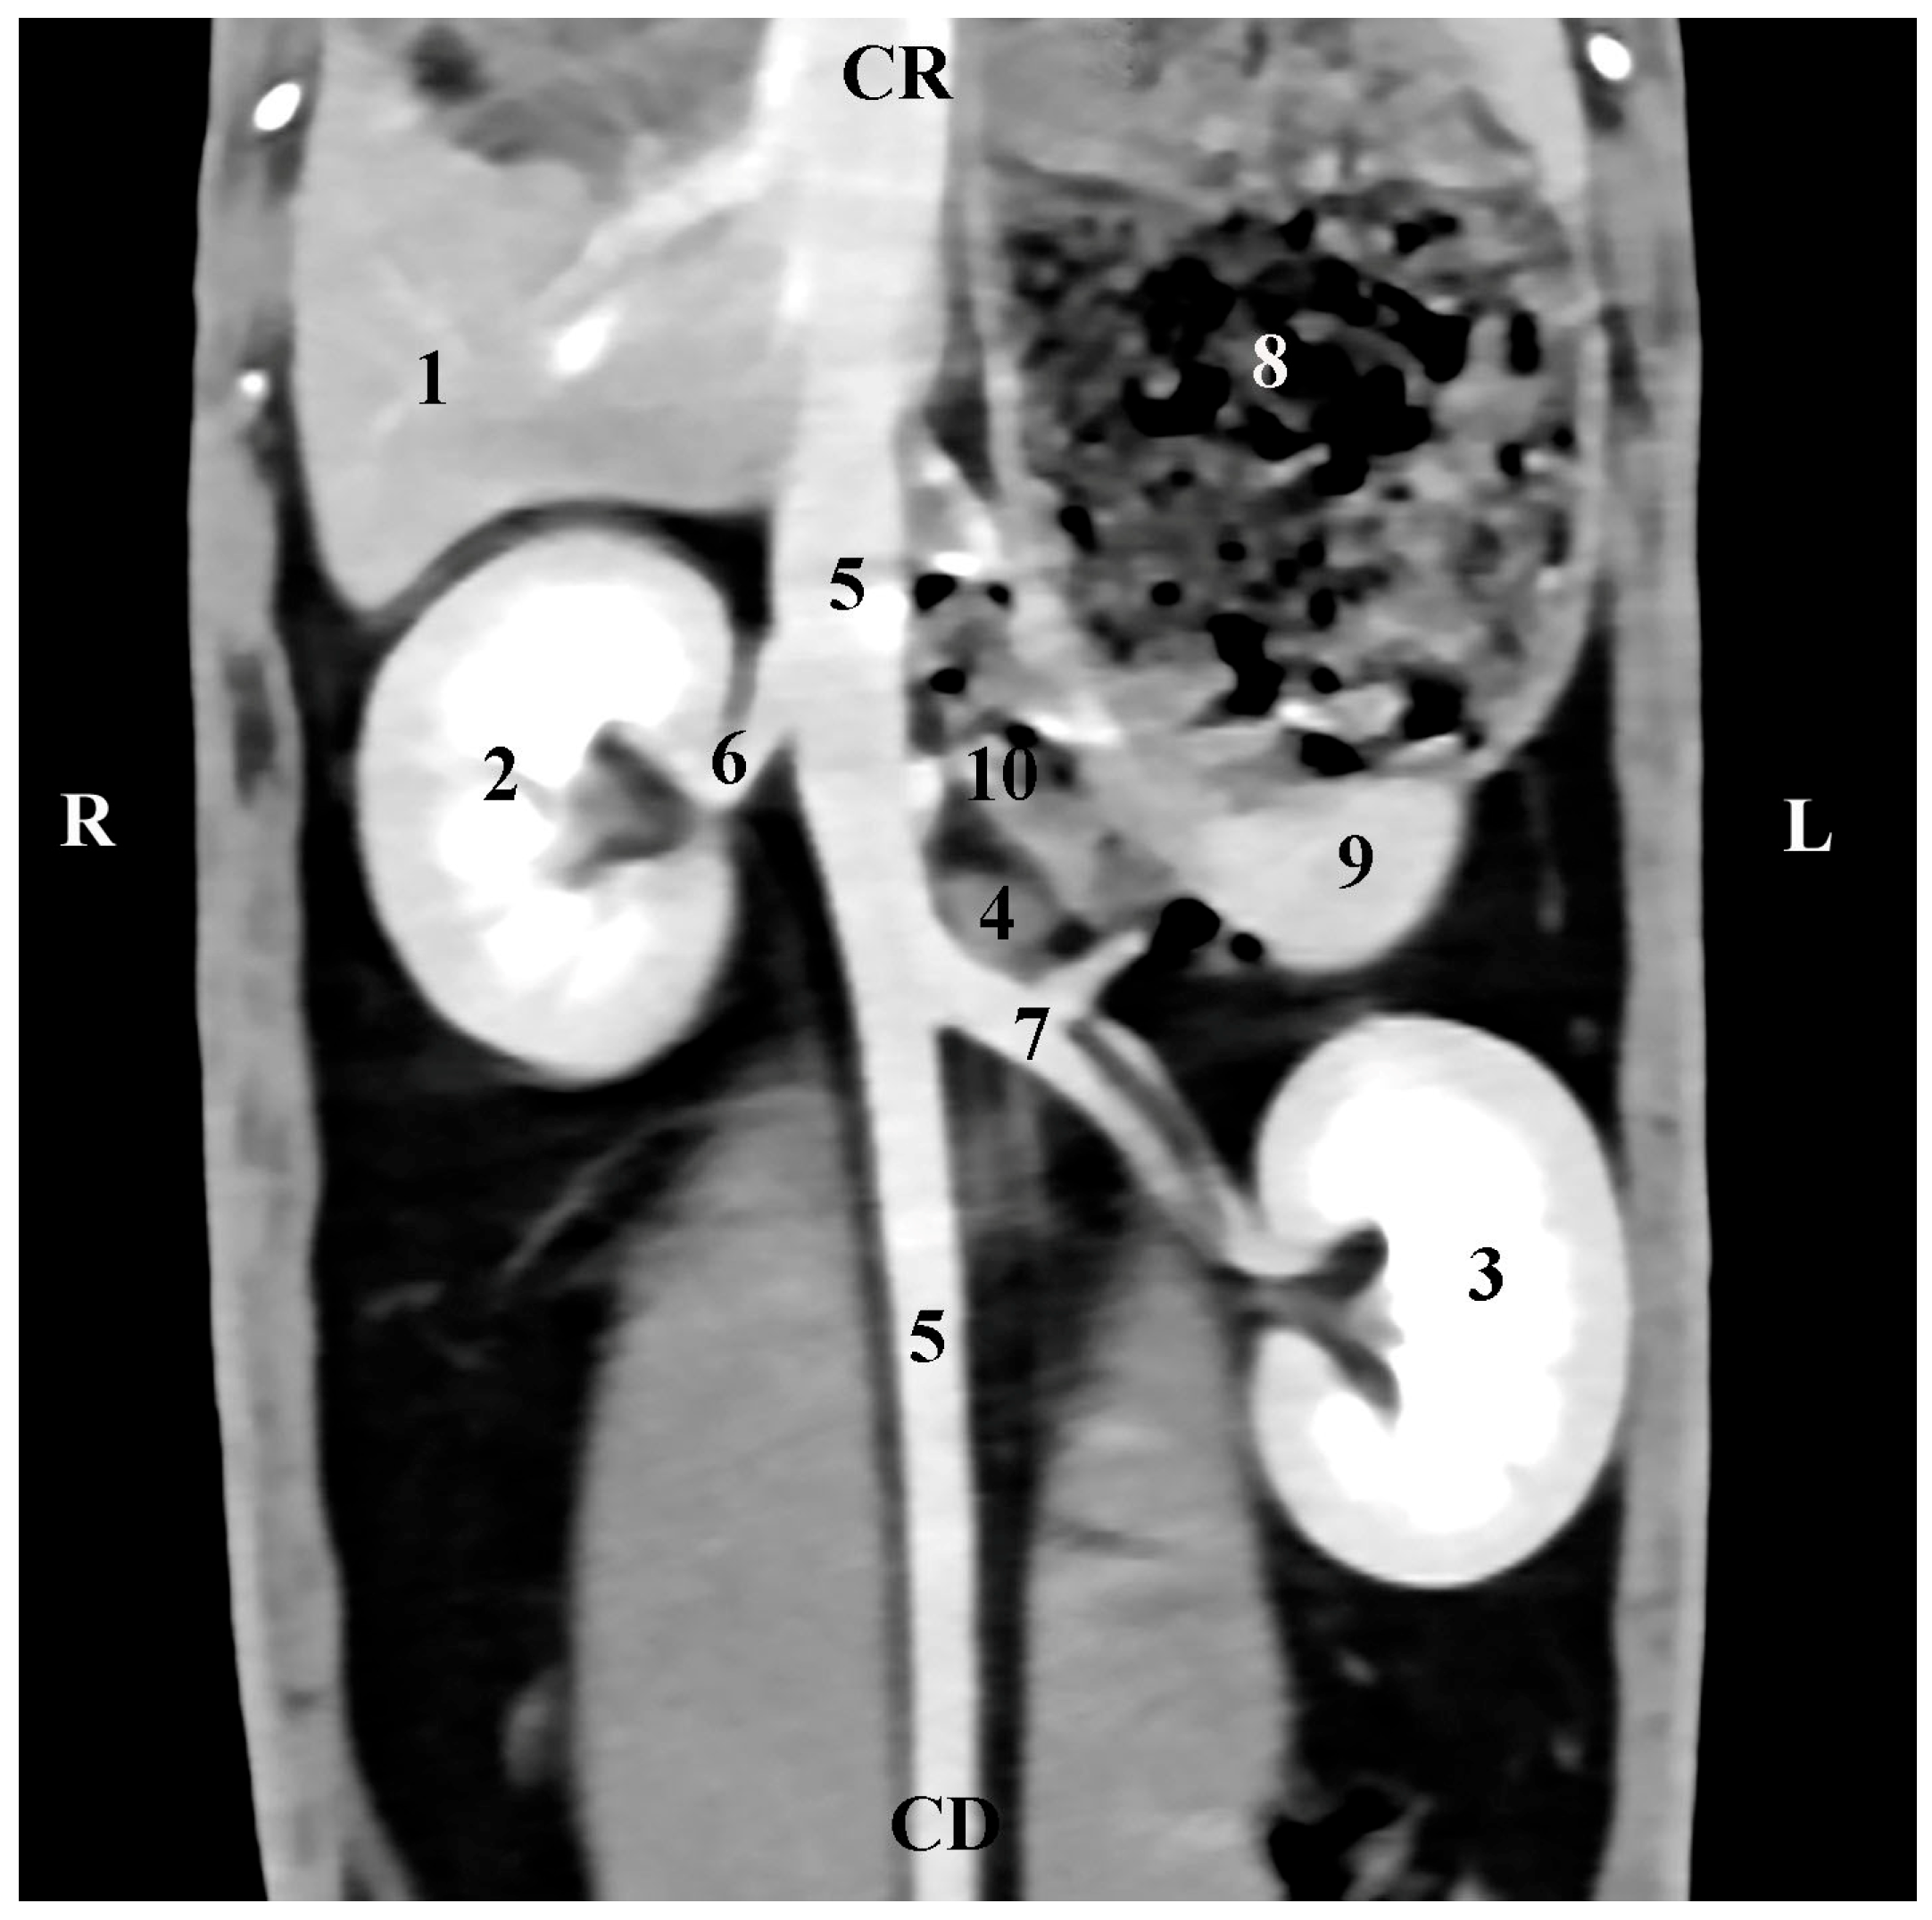

The left adrenal gland was presented at the subsequent scanning level (45 mm ventrally to the spine). Its localization was in the regio abdominis lateralis sinistra of the regio abdominis media. The soft tissue features of the gl. adrenalis sinistra had a lower degree of attenuation in relation to the contrast-enhancing abdominal aorta, with which the gland was in direct contact medially. The contrast-enhancing a. renalis sinistra was observed caudally to the left adrenal gland, and the contours of the pars ascendens duodeni were seen cranially. The gland shape was oval. Unlike the right adrenal gland, the left gland was at a significant distance from the hyperattenuated left kidney (Figure 6).

Figure 6. Dorsal (coronal) CT post-contrast anatomical study of the rabbit abdomen (at the plane 45 mm ventral from the vertebral column). CR—cranial; CD—caudal; R—right; L—left. (1) Liver; (2) right kidney; (3) left kidney; (4) left adrenal gland; (5) aorta abdominalis; (6) a. reanlis dextra; (7) a. renalis sinistra; (8) fundus et corpus ventriculi; (9) spleen; (10) pars ascendens duodeni.